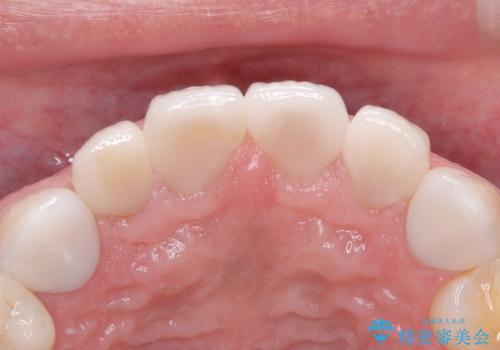

【セラミッククラウン】他院で治療したセラミッククラウンをやりかえたい

- 他院で1年ほど前にセラミッククラウンを入れたそうですが、しばらくしてから歯茎から膿が出てきたそうです。

歯髄診にて歯髄が失活していることが判明したため、クラウンを除去し根管治療を行ってから、再度オールセラミッククラウンを作成しています。

今回のケースはクラウン除去した際に露髄点は認められなかったため、形成時の発熱が原因であったと推測しています。